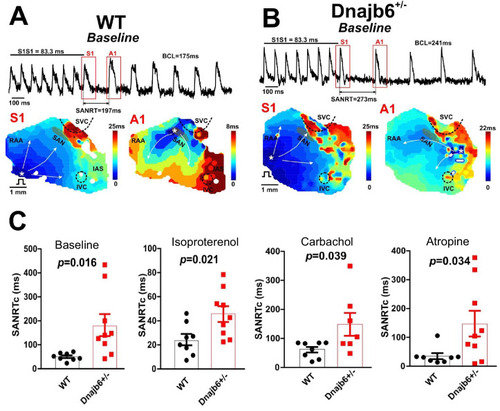

Sinus node recovery time was prolonged in the Dnajb6+/- mice. (A–B) Representative activation maps reconstructed for the last pacing stimulus (S1) and the first spontaneous post-pacing atrial beat (A1) during SAN recovery time (SANRT) measurements are shown. A site of the earliest atrial activation is labeled by a white asterisk. In Dnajb6+/- group, unlike WT, the first spontaneous post-pacing atrial beat (A1) originated from an ectopic location outside of the anatomically and functionally defined SAN area. (C) Summarized data for corrected SANRT (+/-) measured during different autonomic stimulations is shown. N=7–9 mice per group, unpaired student’s t-test. |